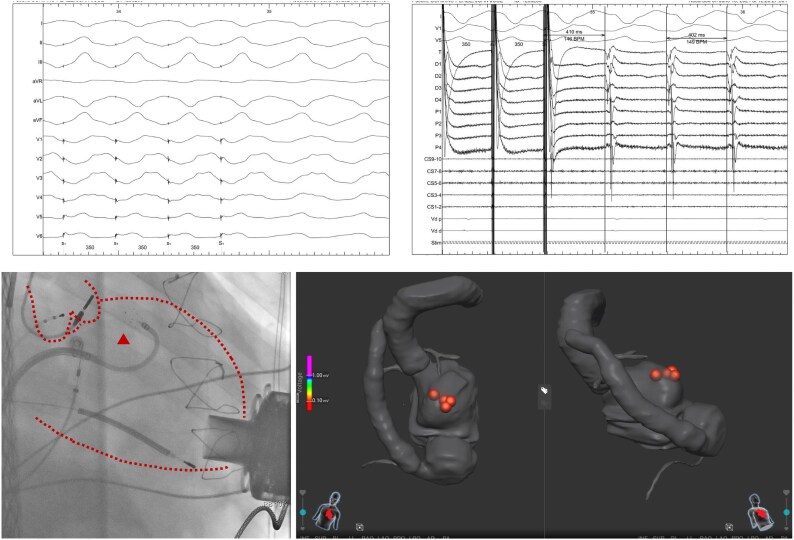

背景:室性心动过速(vt)是终末期左心室功能障碍患者的一种危及生命的并发症,也是考虑先进治疗的常见原因。在左心室辅助装置(LVAD)支持的患者中,他们的管理提出了独特的挑战,需要多学科的方法来定制策略。病例总结:我们报告一位有室性心动过速病史的70岁男性患者,因继发于缺血性心肌病和难治性室性心动过速的晚期心力衰竭而接受心脏伴侣3 (Abbott, USA)植入。在LVAD植入后,他开发了一种电风暴,对抗心律失常药物和射频和脉冲场导管消融的组合难以耐受。由于持续的VT,交感神经系统的神经调节被认为是最后的策略。经皮射频消融星状神经节不成功;而左侧交感神经切除术能有效控制心律失常。随访1年,患者无心律失常事件发生。讨论:LVAD携带者的室性心动过速的管理通常是逐步进行的,从纠正可逆的触发因素和使用抗心律失常药物开始。然而,单一治疗往往是不够的,实现心律失常的控制往往取决于多模式的方法。对于常规措施无效的病例,升级到导管消融、神经调节技术和立体定向心律失常放射消融可能是有效的。

Case summary: We present the case of a 70-year-old male with a history of VTs who underwent HeartMate 3 (Abbott, USA) implantation for advanced heart failure secondary to ischaemic cardiomyopathy and refractory VTs. Following LVAD implantation, he developed an electrical storm refractory to a combination of antiarrhythmic drugs and both radiofrequency and pulse-field catheter ablations. Due to persistent VT, neuromodulation of the sympathetic nervous system was considered as a last-resort strategy. Percutaneous radiofrequency ablation of the stellate ganglion was unsuccessful; however, left surgical sympathectomy effectively controlled the arrhythmias. The patient has remained free of arrhythmic events at 1-year follow-up.